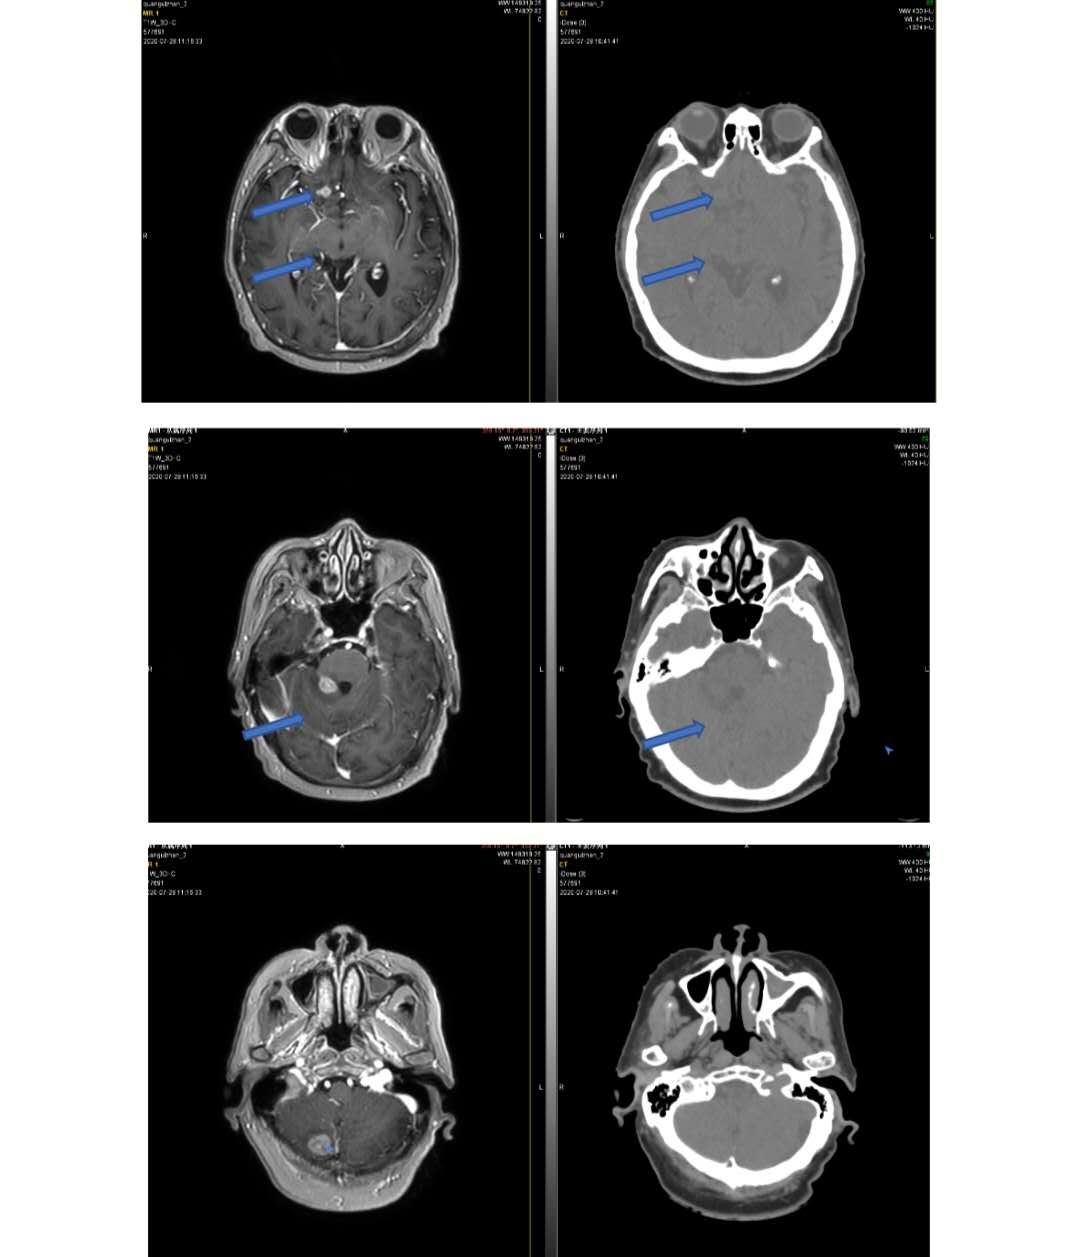

图4-6为一直肠癌脑转移患者的定位图像,MR增强图像较CT图像更加清晰。MR定位的多方位、多参数、多轴倾斜切层对中枢神经系统病变的定位定性诊断极其优越。

图4-6直肠癌脑转移,MR增强序列vs CT